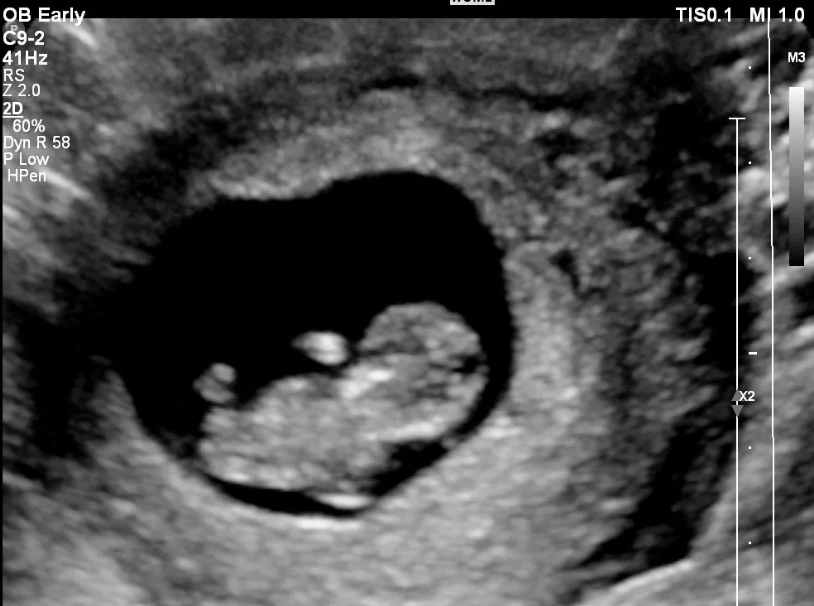

The Medical Screening: The Nuchal Translucency (NT) Scan

This is the core of the 12-week ultrasound. The sonographer takes a very precise measurement of the fluid-filled space at the back of your baby's neck. This is the nuchal translucency. All babies have some fluid there, but an increased measurement can be a soft marker for certain chromosomal conditions, like Down syndrome (Trisomy 21).

It's critical to understand: An increased NT measurement is NOT a diagnosis. It's a risk assessment tool. The measurement is combined with a blood test (the first part of the integrated or combined screening) and your age to calculate a probability. I've seen many parents spiral into anxiety over a slightly thick NT scan, only to have a perfectly healthy baby. The scan is a piece of a puzzle.